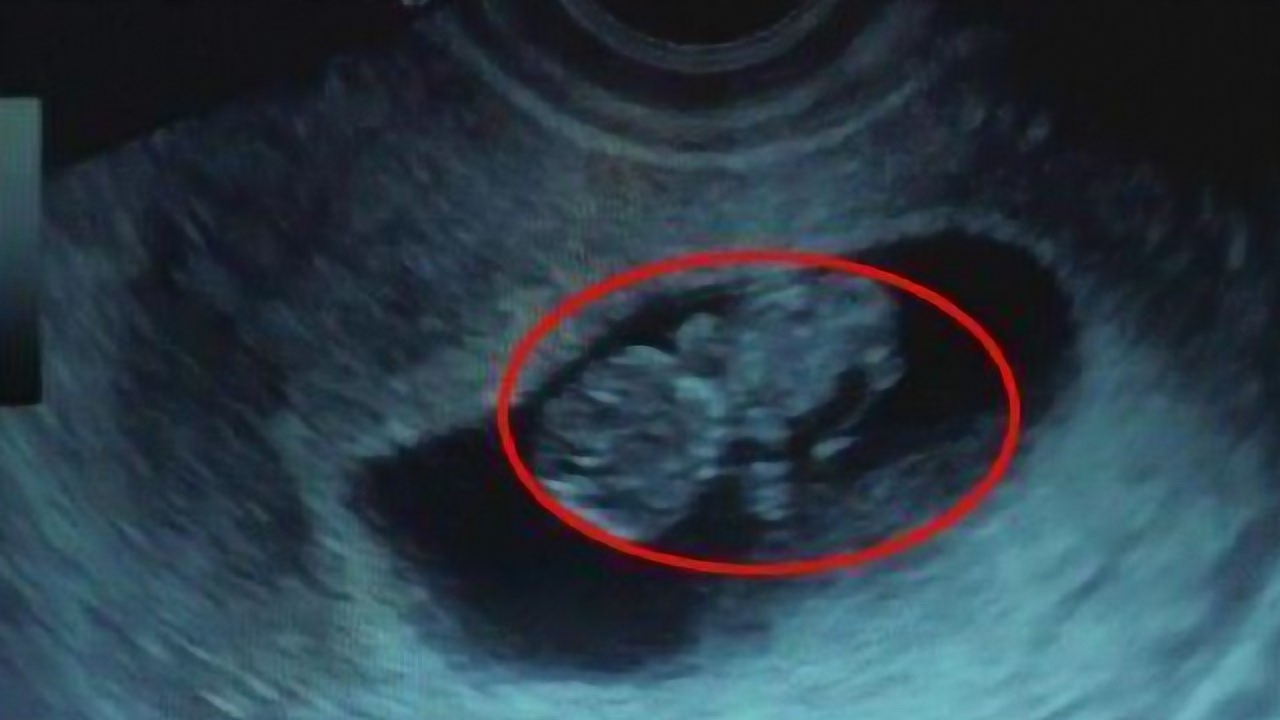

63天的胎儿有多大图片

63天的胎儿有多大图片,怀孕63天胎儿图片

怀孕63天胎儿图片

怀孕63天宝宝图片

怀孕63天胎儿发育图片

怀孕63天胎儿b超图